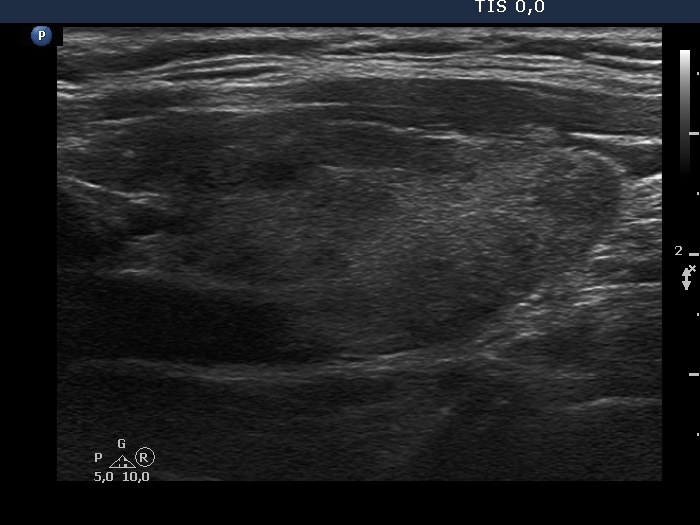

Discrete lesion or nodule in Hashimoto's thyroiditis - case 25 (571)

Second examination two years later (ultrasonographic picture 6)

Left lobe longitudinal scan. The discrete areas in this lobe are also better demarcated.